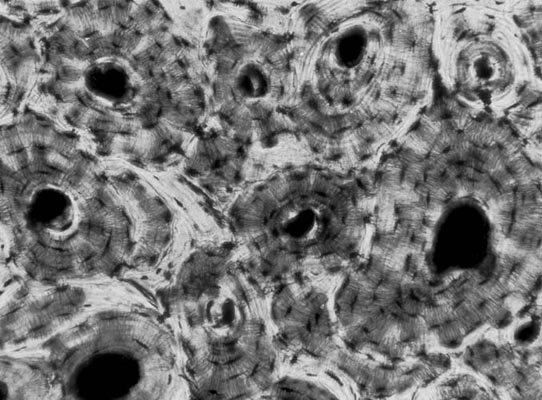

Compact bone tissue photographed with T-max 100 film through a Nikon light microscope using Köhler illumination and a single lens reflex camera. |